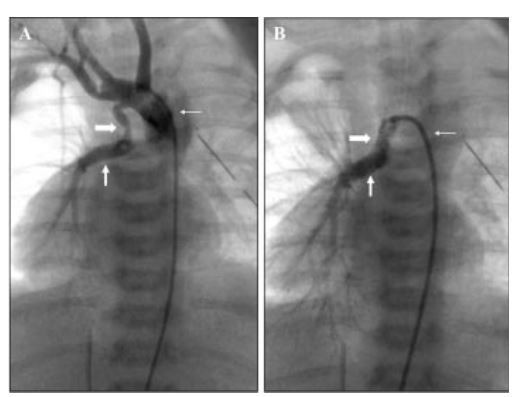

En tres pacientes de entre 2 y 9 días de vida con atresia pulmonar se colocaron cuatro stents por cateterismo, sin complicaciones. El tiempo de seguimiento promedio fue de 411 días (123 a 721 días). Dos stents se redilataron exitosamente. Un paciente fue sometido a cirugía, uno interrumpió sus controles cuatro meses después y otro espera cirugía. La saturación promedio aumentó del 61% al 80%.

En pacientes con cardiopatías cuya circulación depende del ductus arterioso, el implante del stent fue factible y efectivo a corto y mediano plazos.